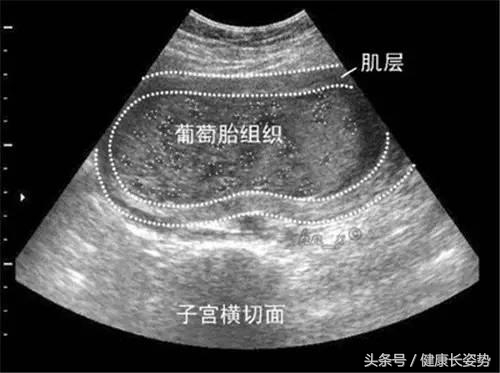

葡萄胎是由于滋养层细胞增生和绒毛间质水肿。许绒毛变成了大小不等的水泡,相互间有细蒂相连,如葡萄状,所以称作葡萄胎。葡萄胎有两种:

葡萄胎的诊断主要依靠B超,无胎心及羊水,出现密集的中、小波;尿或血的HCG的测定。孕妈已经确诊,应该立即住院治疗。